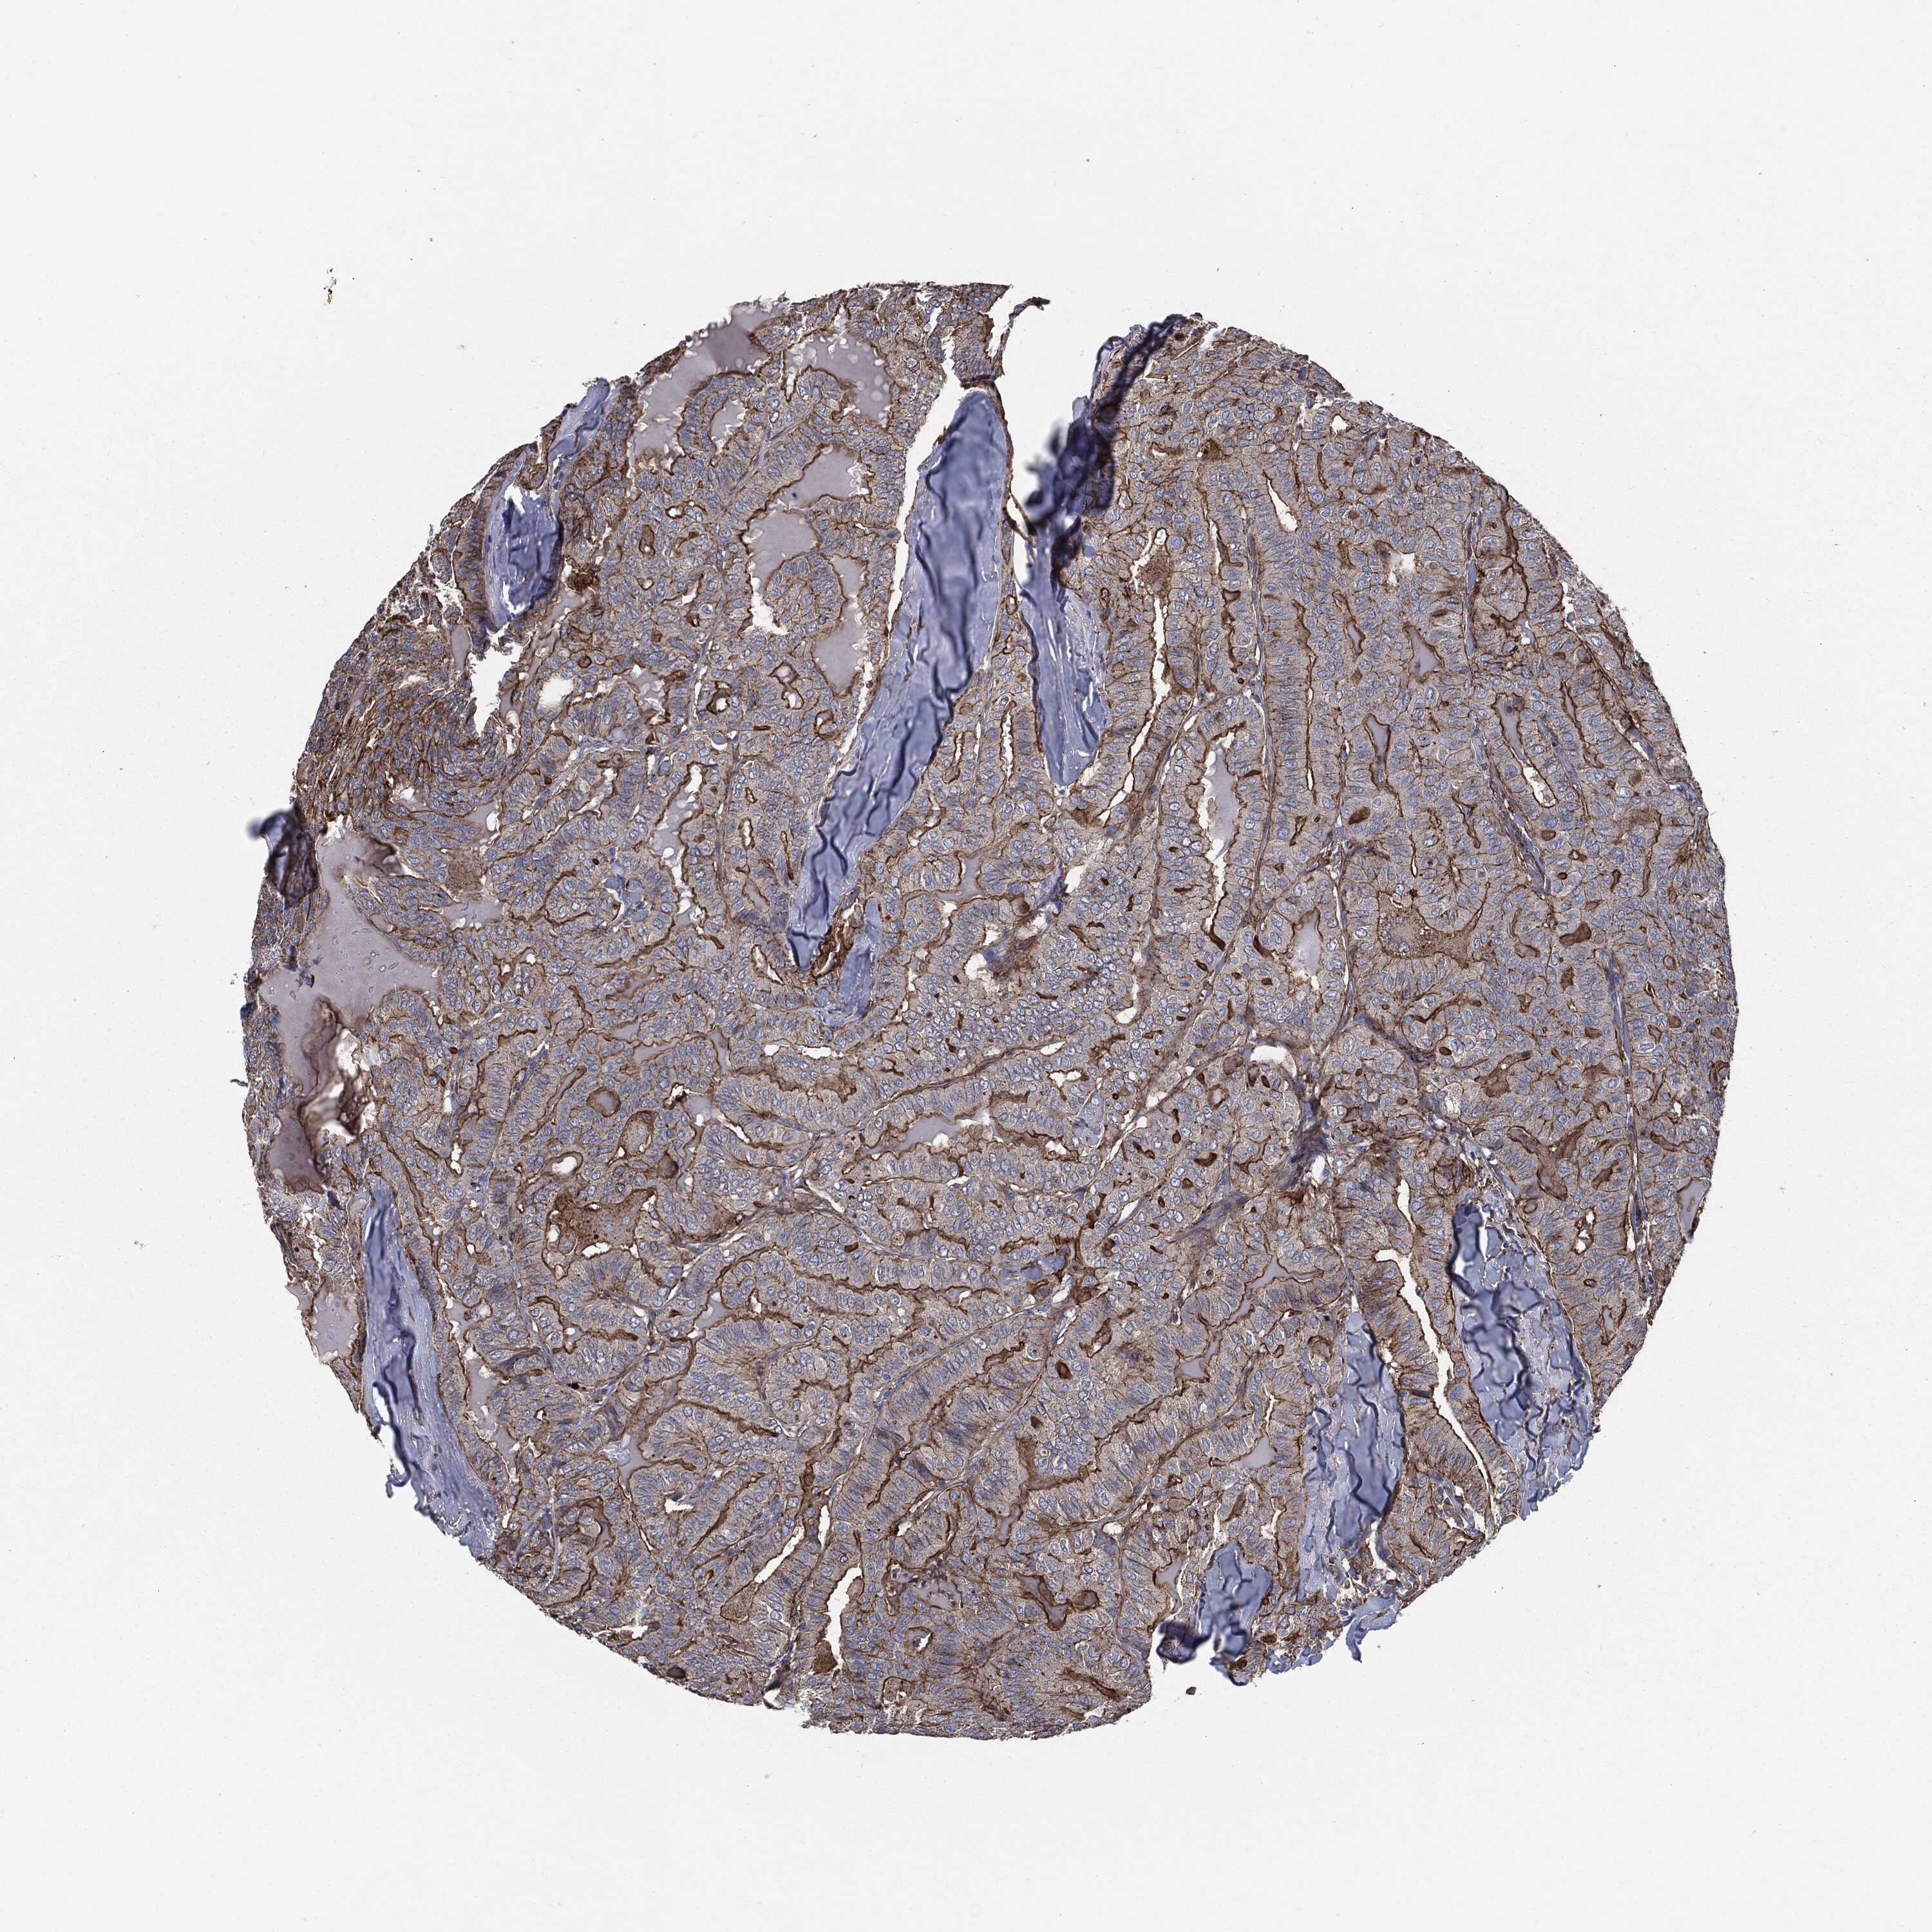

THYROID CANCER - Protein expressioni

A mouse-over function shows sample information and annotation data. Click on an image to view it in a full screen mode. Samples can be filtered based on level of antibody staining by selecting one or several of the following categories: high, medium, low and not detected. The assay and annotation is described here.

Note that samples used for immunohistochemistry by the Human Protein Atlas do not correspond to samples in the TCGA dataset.

Antibody stainingi

Antibody staining in the annotated cell types in the current human tissue is reported as not detected, low, medium, or high, based on conventional immunohistochemistry profiling in selected tissues. This score is based on the combination of the staining intensity and fraction of stained cells.

Each image is clickable and will lead to virtual microscopy that enables deeper exploration of all samples and also displays staining intensity scores, fraction scores and subcellular localization as well as patient and tissue information for each sample.

Antibody HPA020095

Antibody HPA020138

Antibody CAB010878

Antibody CAB080402

Staining

High

Medium

Low

Not detected

Intensity

Strong

Moderate

Weak

Negative

Quantity

>75%

75%-25%

<25%

None

Location

Nuclear

Cytoplasmic/membranous

Cytoplasmic/membranous,nuclear

Papillary adenocarcinoma, NOS

Follicular adenoma carcinoma, NOS